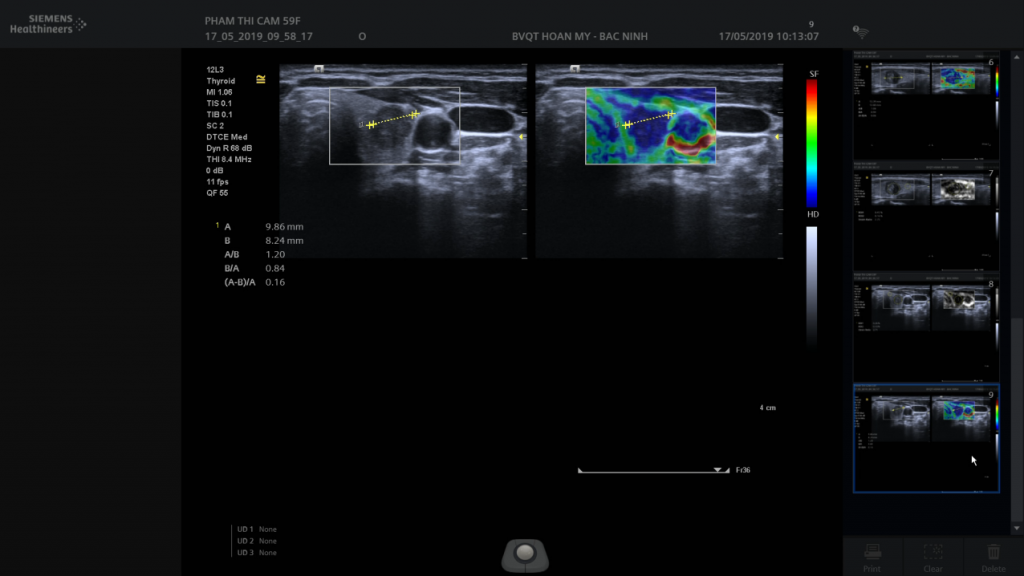

Hình 1. Hình ảnh trên siêu âm đàn hồi mô

• Siêu âm đàn hồi mô tuyến giáp: Chẩn đoán các nốt tuyến giáp. Khi làm siêu âm B mode thấy một tổn thương khu trú, bên cạnh việc nhận định hình thái tổn thương, chúng ta phân loại theo TIRADS để nhận định mức độ lành hay ác tính, thăm dò Doppler để đánh giá tình trạng tưới máu, và làm Elastogram để nhận định độ cứng sẽ cho phép đánh giá tính chất lành tính hay ác tính của tổn thương chính xác hơn và chỉ định sinh thiết chuẩn xác hơn.